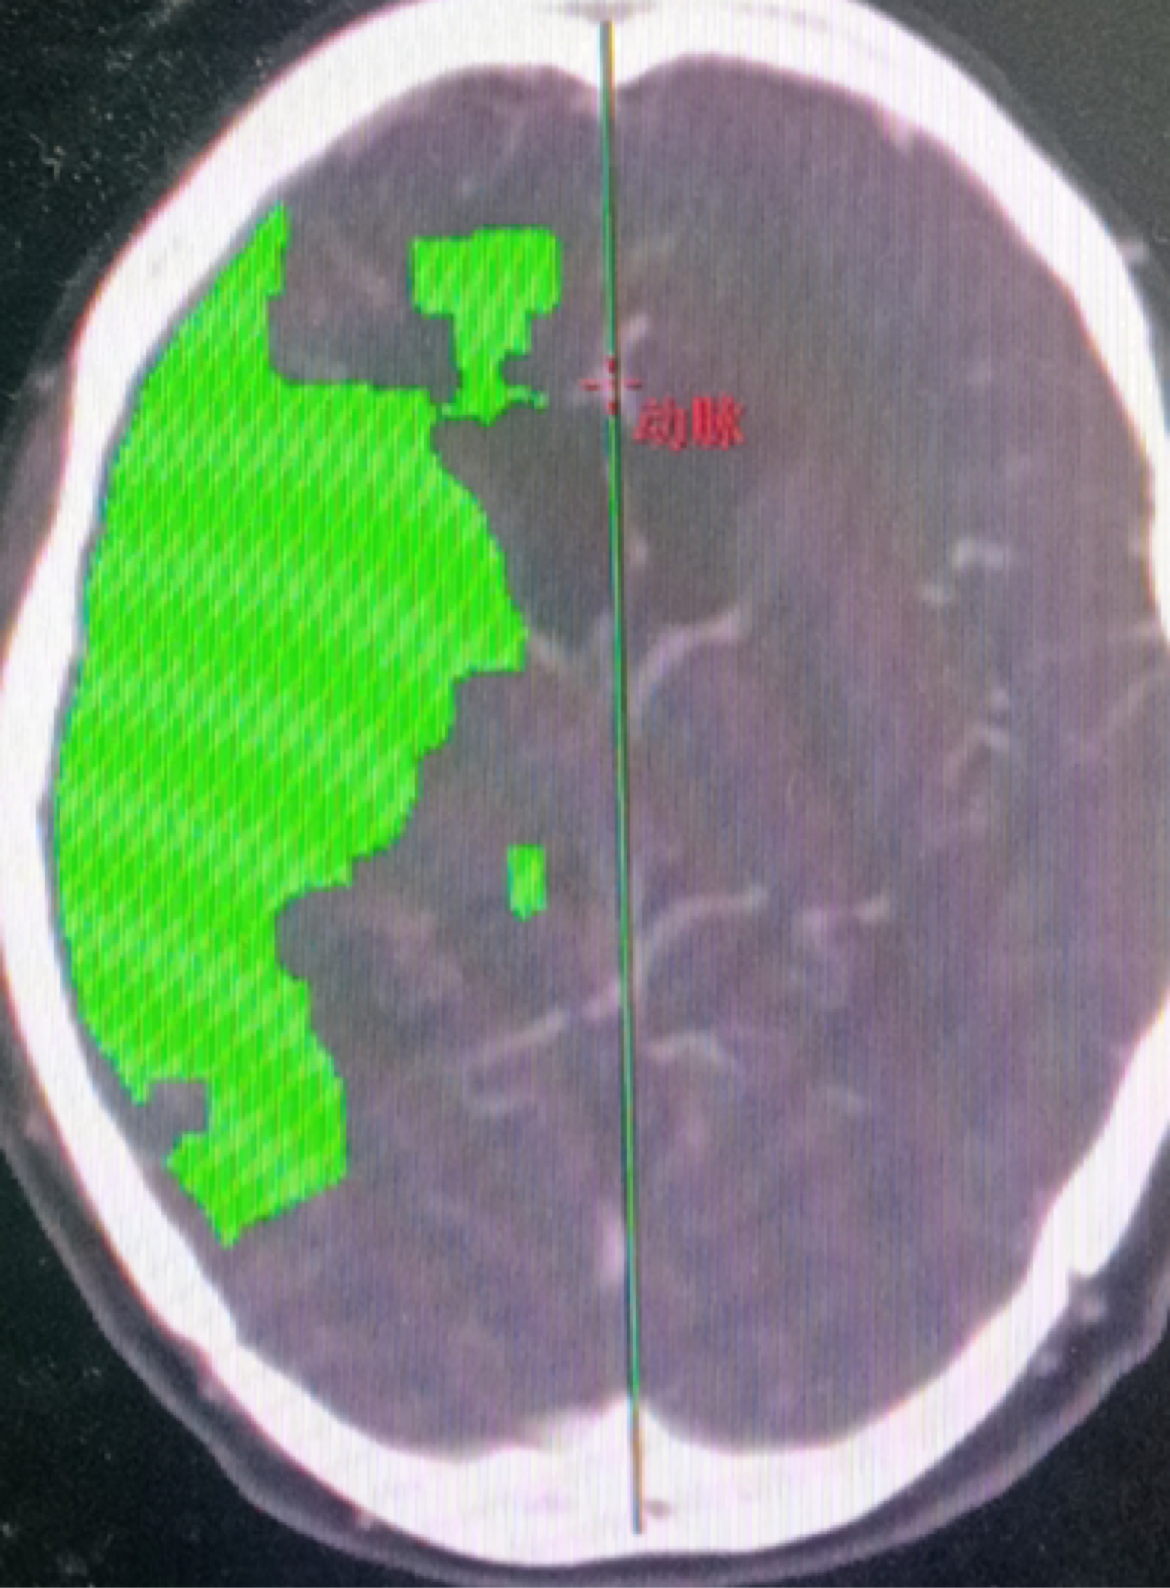

脑灌注提示右侧大脑半球低灌注